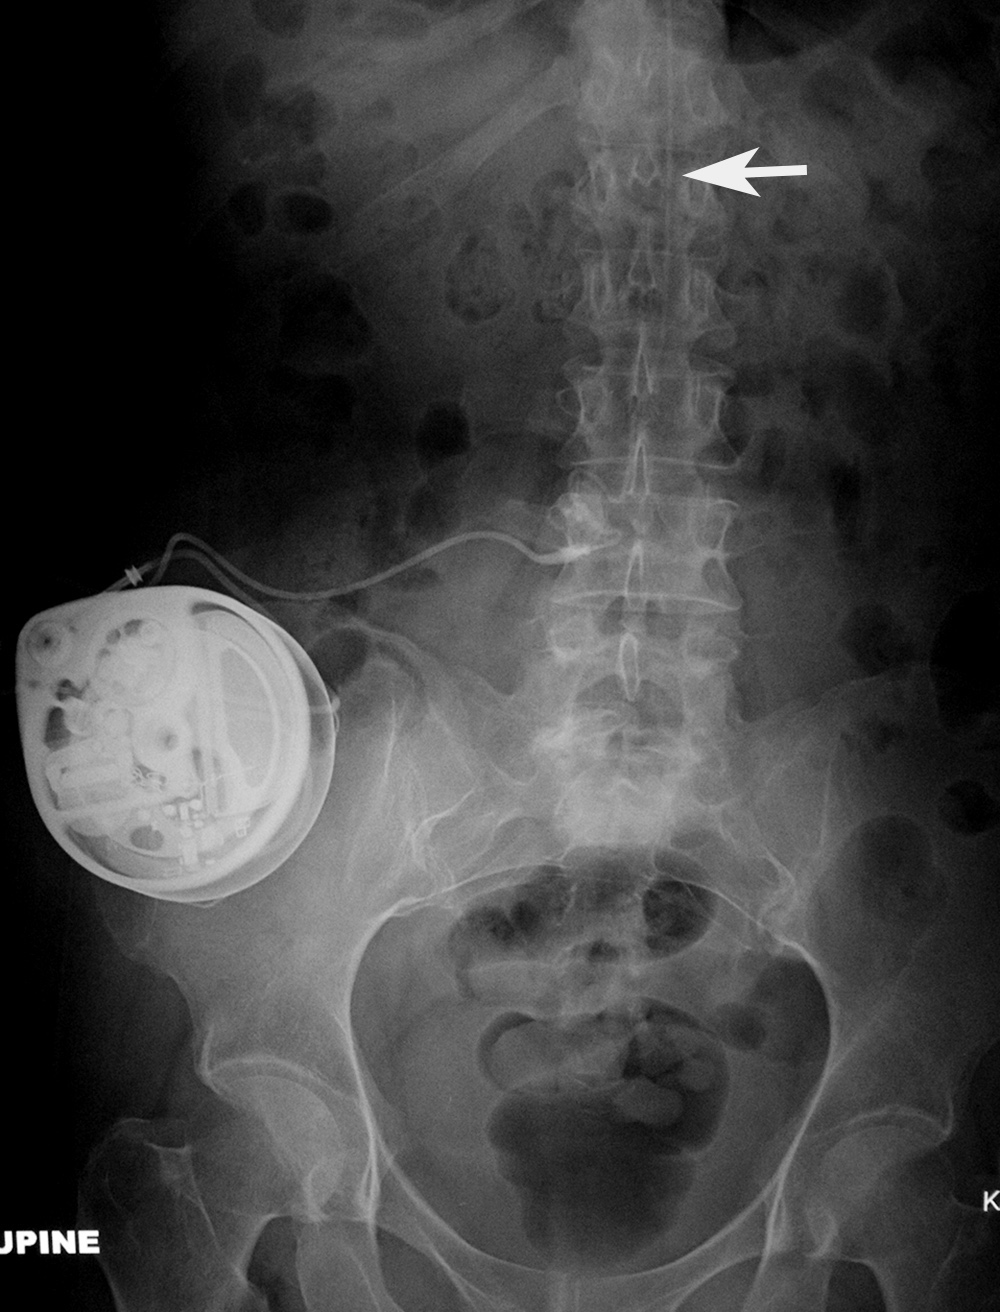

Baclofen intrathecal delivery pump AP view |

Baclofen intrathecal delivery pump lateral view |

The catheter (arrow) goes into the lower thoracic spinal subarachnoid space. |

The catheter (arrow) goes into the lower thoracic subarachnoid space. |

| Intrathecal drug delivery catheter (arrow) |

| The catheter is in the lower thoracic subarachnoid space. It exits in an anterior abdominal delivery pump. From Hunter, 2004 |